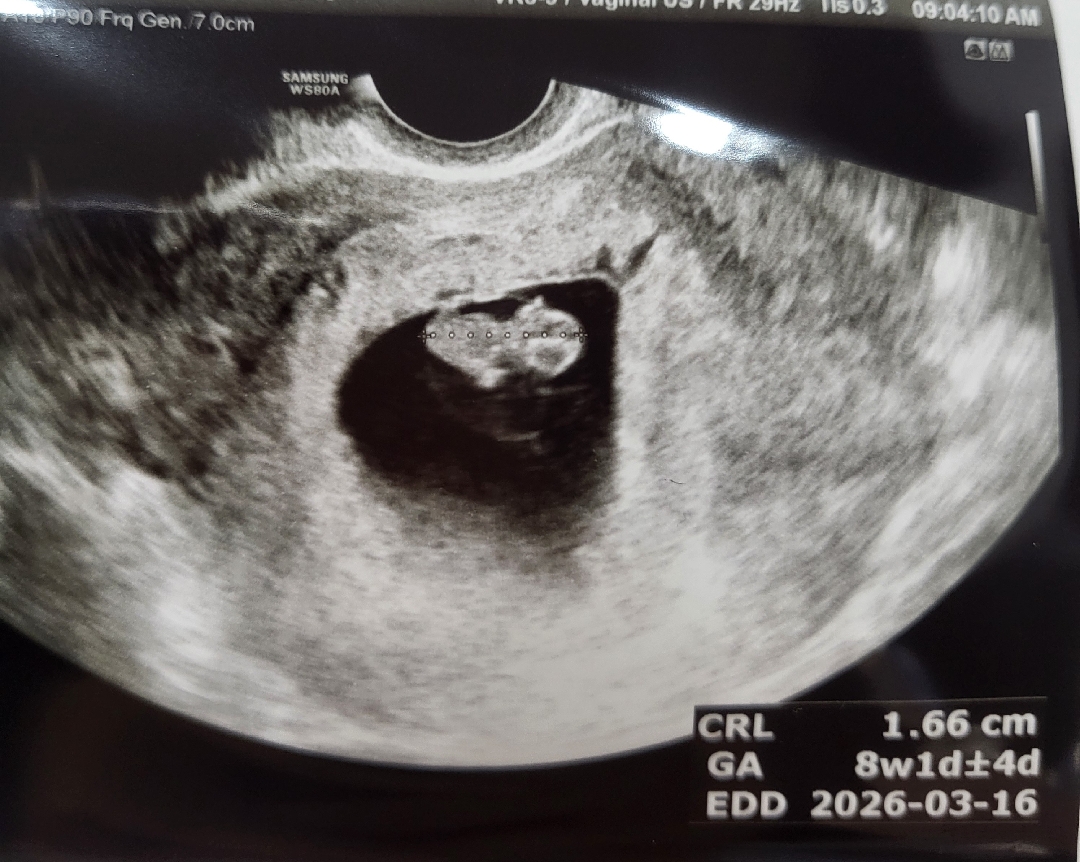

8주 1일에 본 젤리곰! 조랭이떡?

2주 만에 보러가서 잘 있나 궁금했었는데 0.3cm에서 그새 1.3cm나 더 컸더라구요 심장박동도 100이었는데 180으로! 주수대로 잘 크고 있다고 해서 다행이었어요 이제 3주뒤에 가야되지만 그래도 저번보단 더 잘 기다릴 수 있을 것 같아요 ㅋㅋ